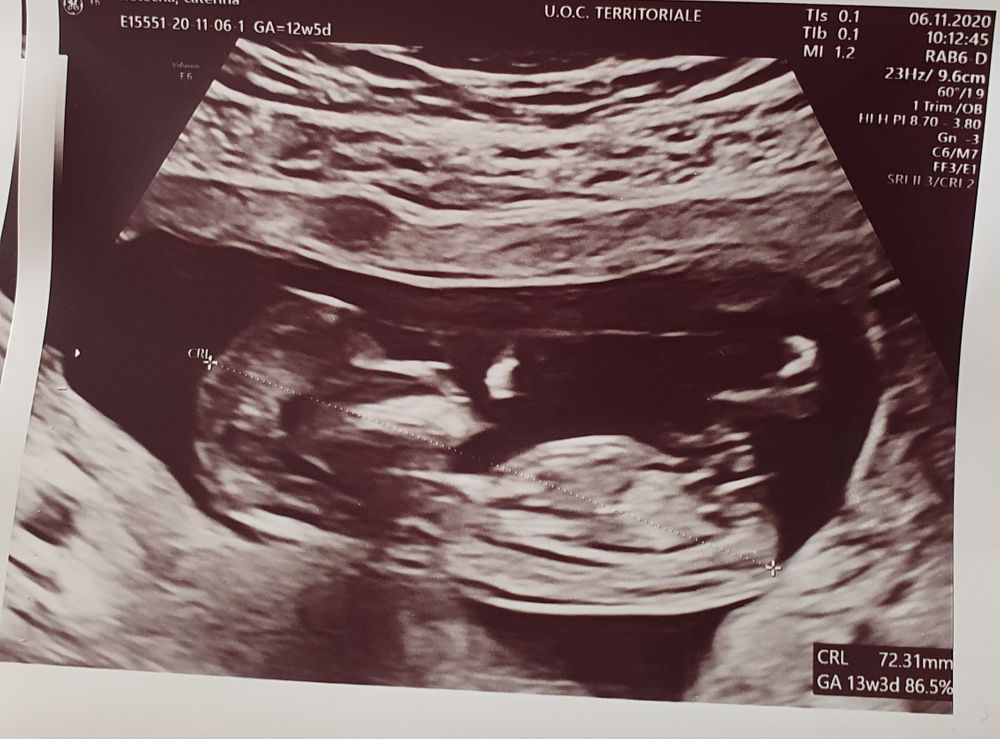

Узи первого триместра

Очень волновалась перед узи, но как только увидела мою крошку на экране, волнение как рукой сняло 🥰, такой там человечек большой уже, пальчик сосал, пока мы на него смотрели)))

По кд сегодня 12+5, по узи 13+2

Ктр 67 мм

Бпр 21 мм

Твп 1.10 мм

Чсс 152

Носовая кость присутствует